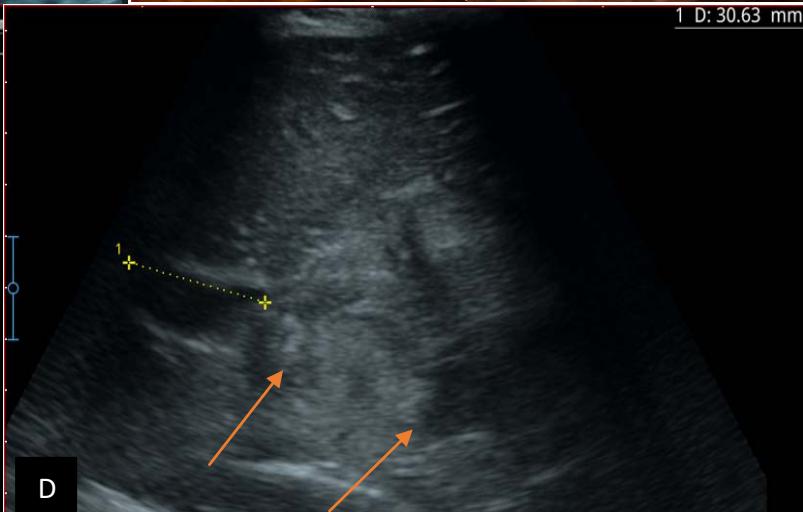

Figure 5: Abdominopelvic ultrasound control after 6 courses of chemotherapy in the same 3 year old patient with a ruptured left renal nephroblastoma; Images A, F, G, and H: show regression of the solid, endo and exo renal, left nephroblastoma mass treated with 6 courses of chemotherapy (current volume 430 ml vs) Images: B, C, and: show persistence of thrombotic permeation pan vena cava and ipsilateral renal. Image E: shows a volumetric regression of the intra-lesional hematic collection, at the tumor rupture estimated at 34.49 ml VS, Image I: represents the right kidney in B mode which is of normal echoculture. Source: Dr. Frederick Tshibasu Tshienda database.

Figure 6: 9-year-old sickle cell patient, referred for abdominal bloating with significant collateral venous circulation, in whom we noted: Image A: mass, Image B: healthy renal stump, inferior polar; Image C: left transmedian extension, Image D: thrombosis of the vena cava segments: supra, retro and sub hepatic, sparing a part of the supra hepatic vena cava segment over $30~\mathrm{mm}$. Image: Ascites of great abundance, Image F: normal left kidney, Image G: splenic microcalcifications, Image H: celiac adenopathy, Image I: sub pleural pulmonary nodules with the biggest measuring $3.88 \times 3.81 \mathrm{~mm}$, Image j: left pleurisy of great abundance. Source: Dr. Frederick Tshibasu Tshienda database.